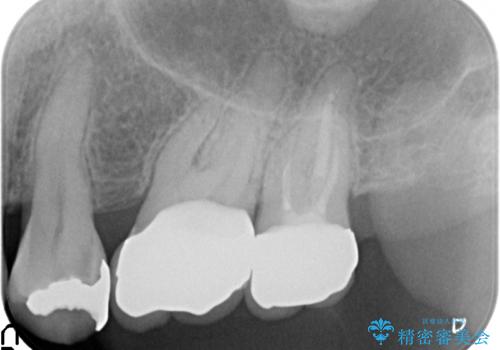

治療後はしみなくなり、違和感のない自然な咬み心地にご満足頂けました。

「割れる心配のないゴールドにしたいけれど、目立ってしまうかしら...」と心配されており、不要に歯質を削合しないよう注意を払い最小限の大きさのインレーを装着したところ、「あまり目立たなくて良かった!」とおっしゃって下さいました。